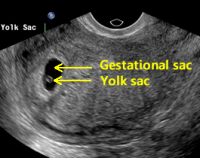

So these 2 are 5 week ultrasounds.

The bottom s the closest as to what mine looks like. And I'm pretty sure the sac went from leg tto right, a decent size and the halo was more i the middle.

From what I'm reading, the gestational sac is all the black. And the white is the halo looking image. I have that halo.

But they said all I have is a gestational sac. And I am measuring 5wks 1 Day. But its been 6 weeks since implant.

My HCG this time dropped from 880 to 811. Slight. From what Im reading that what I saw on mine is the normal fr 5 weeks.

But yet they said all I have is the sac. I don't understand.